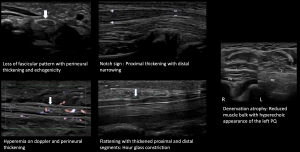

Nerve pathology can present with a variety of imaging appearances, depending on the degree and pattern of injury [7]. Common US findings in peripheral nerve pathology include nerve thickening, loss of fascicular appearance, perineural thickening, hyperemia, notch sign, hourglass constriction, and denervation of muscle groups, as demonstrated in